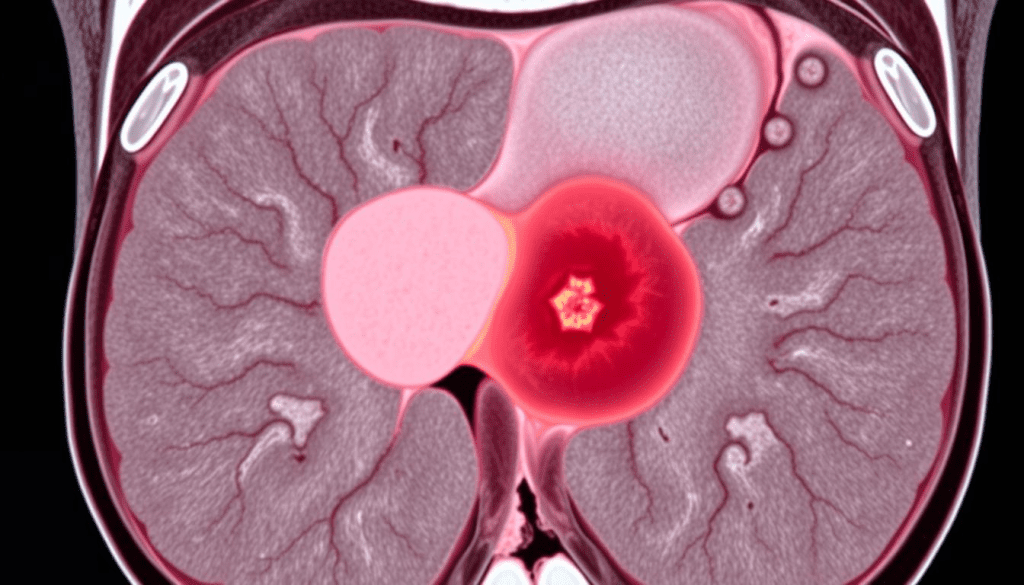

Advanced Imaging Techniques for Measuring Hepatoblastoma

We use top-notch imaging to check the size and spread of hepatoblastoma tumors in the liver. MRI and CT scans are key in measuring these tumors accurately.

Measuring hepatoblastoma right is key for treatment planning. When tumors are found in multiple sites in the liver, knowing their size and location is critical. This helps in planning surgery and understanding the patient’s outlook.

Clinical Implications of Multiple Tumor Sites

Having tumors in multiple sites makes treatment more complex. It needs a detailed plan for surgery and chemotherapy. Advanced imaging helps pinpoint the tumors’ exact spots and sizes, leading to a more personalized treatment.

When there are multiple tumor sites, the team must think about the liver’s function and how treatment might affect the patient’s life. Our team of experts works together to create a detailed treatment plan.

Advanced imaging is not just for the first check-up. It also helps track how well treatment is working. This allows for changes in the treatment plan as needed. This flexible approach is key to better outcomes for patients with hepatoblastoma.